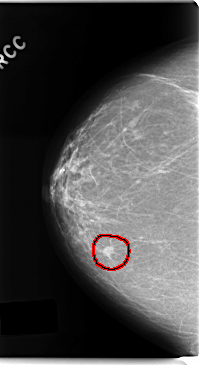

C_0192_1.RIGHT_CC

FILE: C_0192_1.RIGHT_CC.OVERLAY

TOTAL_ABNORMALITIES 1

ABNORMALITY 1

LESION_TYPE MASS SHAPE OVAL MARGINS SPICULATED

ASSESSMENT 5

SUBTLETY 5

PATHOLOGY MALIGNANT

TOTAL_OUTLINES 1

BOUNDARY